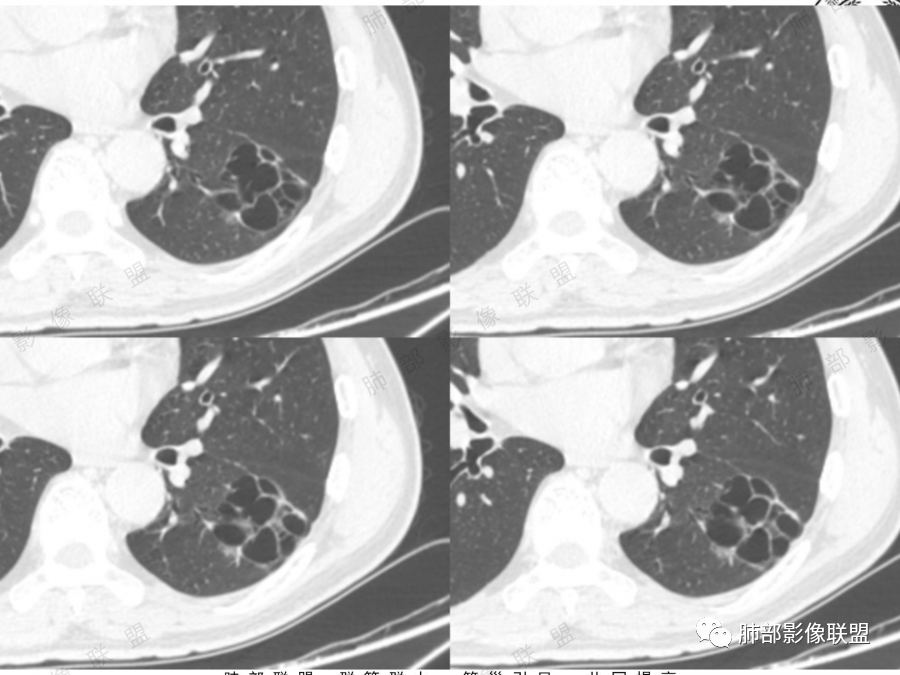

左肺下叶空腔,分隔状,壁厚薄不均,支气管截断,部分周围可见磨玻璃影,胸膜牵拉,左肺上叶多发结节,部分可见钙化,考虑1左肺下叶囊腔型腺癌。2左肺上叶结核。

中年男性,多发空腔,腔内可见分隔、壁结节。考虑:囊腔型腺癌。肺结核为陈旧性。

男51,体检发现肺部阴影,左肺下叶见多发薄壁囊腔影,可见结节,囊腔内见分隔,轻度胸膜牵拉,病灶周围少许磨玻璃影,常规考虑囊腔型腺癌,肿瘤标志物不高,除外结核。

中年男性,体检发现,吸烟史,但肺气肿背景不明显。左肺下叶囊腔病变,有一定张力,分隔明显,似有多个囊腔融合感,部分边缘见少许磨玻璃影,有支气管截断,首选囊腔型肺癌,某些先天病变(囊腺瘤样畸形等)也要考虑。

左肺上叶钙化结节,边界清楚,周围散在多发小结节,伴有磨玻璃影,考虑结核可能,左肺下叶多个囊堆积而成,大小不一,其内可见分隔,囊壁厚薄不均,病变近端与支气管相贴,支气管似扩张,考虑CCAM,鉴别囊腔性腺瘤,囊腔性腺癌

肺结核背景,左下肺簿壁囊腔,内有分格,有支气管截断,囊壁局限性增厚,嗜烟史,考虑左下囊腔型肺癌(鳞癌)。

左肺上叶陈旧肺结核,以增殖钙化灶为主,左肺上叶多发囊泡样结节,有分隔,稍分叶,周围少许磨玻璃,支气管部分截断,部分贴边穿过,老年男性,考虑囊腔型腺癌。

左肺上叶多发小结节影,部分钙化,考虑结核。左肺下叶多个囊状影,腔内见血管影,间隔稍粗大,考虑囊腔型肺癌,

老年,51岁男性病人,左上肺斑点,小结节状阴影,可见钙化,陈旧性肺结核改变,患者有长期的吸烟病史。左肺下叶背段多个囊腔肿块影,整体呈团块状类圆型,无明显壁结节,整体病灶张力较大,具备一定的膨胀感 ,支气管拉直并有突然截断改变,考虑囊腔型鳞癌。鉴别诊断:结核性病变,局限性囊性支气管扩张

孤立性的多囊型病变伴分隔。ccam,肺隔离征,囊性肺癌,闭锁。。这是大家上面写的。看看怎么排除。血管看到肺动脉进入供血,没有感染液平,肺隔离不符合。没有代偿肺气肿,支气管没有闭锁,闭锁不考虑。那锁定ccam和肺癌。我们临床也常见是支气管畸形所致的囊。

我们看哪些内容,第1.周围有没有毛玻璃2.分隔有无粗细不均或结节,壁有无厚薄不均有无壁结节3.支气管,4.随访。

图一看到支气管堵塞,不知道是不假象

图二图三似见毛玻璃

另外分隔比较光滑似无壁结节。

男性,体检发现左肺阴影。影像表现:左上肺多发结节伴纤维条索影,部分钙化,左下肺囊腔样改变,内有分隔,部分分隔边缘见实性成分及GGO样改变,支气管从旁边经过,或受压,无明确进入依据。初步诊断:1、左上肺结核。2、左下肺囊腔型腺癌,诊断依据:分隔样囊腔,部分分隔有实变,边缘有GGO改变,鉴别诊断:1、囊腺瘤样畸形,分隔样囊腔要考虑,但部分分隔实变,部分伴GGO样改变成疑,最大的疑问是年龄51岁,体检发现,抽烟、饮酒30年,却无发病,可能性太小。2、囊腔性转移,单发分隔样囊腔转移少见,且需要病史支持。3、囊性淋巴瘤,一般以单发囊腔多见,分隔样囊腔型淋巴瘤罕见。4、感染,无相关临床症状及辅检支持,基本排除。

补充一下,虽然看到有GGO样改变,腺癌可能最大,但如果GGO是假像,有多年吸烟史,也不完全排除囊腔型鳞癌可能。

@傅昌瑜—贺州市人民医院—呼内 里面的血管进一步支持恶性。但不鉴别腺癌和鳞癌,主要鉴别的,还是多囊,张力较高,囊壁较薄(实变区除外),加GGO。